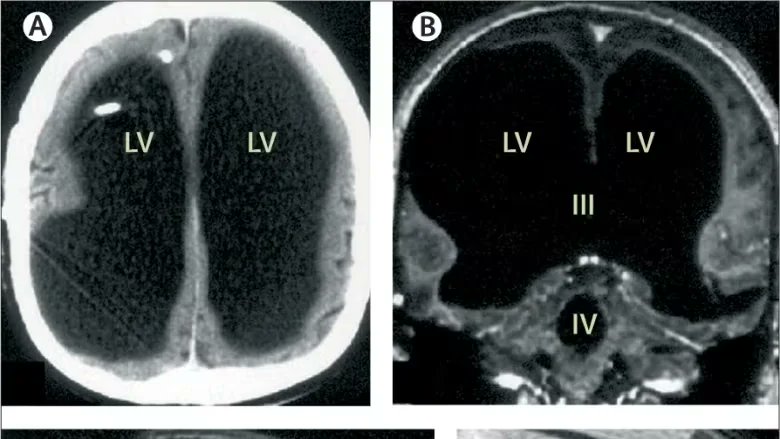

في أحد الأيام، بدأ يشتكي من ضعف بسيط في قدمه اليسرى، قرر الذهاب للطبيب، أجرى الأطباء سلسلة من الفحوصات، بما في ذلك تصوير للدماغ بالأشعة لاكتشاف سبب اعراضه، الذي ظهر في الشاشة صدم الفريق الطبي. كان امامهم فراغ كبير في رأسه.

اظهر الفحص شيئا استثنائيا: كانت جمجمته مليئة بالسائل النخاعي إلى حد كبير ولم يتبقى الا طبقة رقيقة فقط من نسيج الدماغ. تعرف هذه الحالة باسم الاستسقاء الدماغي او hydrocephalus

لكن مدى حالته غير مسبوق،كان فاقد لـ 90% من كتلة دماغه، بمعنى انه يعيش بـ 10% دماغ